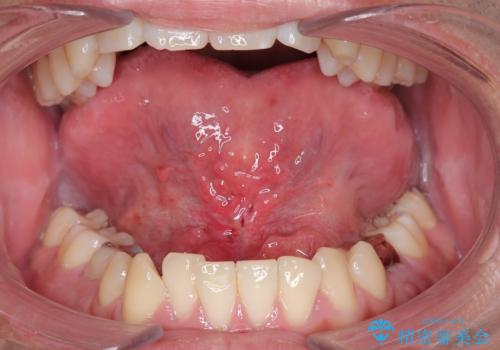

Dr. 長嶋美咲の症例写真

担当医 長嶋美咲<2026年2月4日更新>